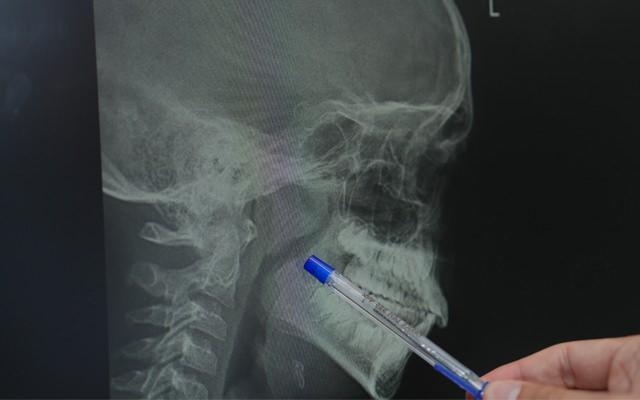

Çocuklarda büyümüş bademcik ve geniz etinin yalnızca fizikî değil, gelişimsel riskler de taşıdığını söyleyen Çelik, “Tedavi edilmediğinde büyüme ve gelişme geriliği, yüz yapısında bozulma, sık orta kulak enfeksiyonu ve okul muvaffakiyetinde düşüş üzere sonuçlarla karşılaşabiliyoruz” ikazında bulundu. Her bademcik probleminin bademciğin büsbütün alınmasıyla sonuçlanmayacağını lisana getiren Dr. Çelik, “Eğer hastamız sık bademcik enfeksiyonu geçirmiyorsa ve yalnızca hava yolu tıkanıklığı varsa bademcik küçültme süreciyle sorun çözülebilir” dedi.

Ameliyat tekniklerine de değinen Dr. Çelik, geniz eti operasyonlarının klasik yahut buharlaştırma metoduyla yapılabildiğini belirtti. Bademcik ameliyatlarında ise sıcak ve soğuk formüller kullanıldığını söyledi.